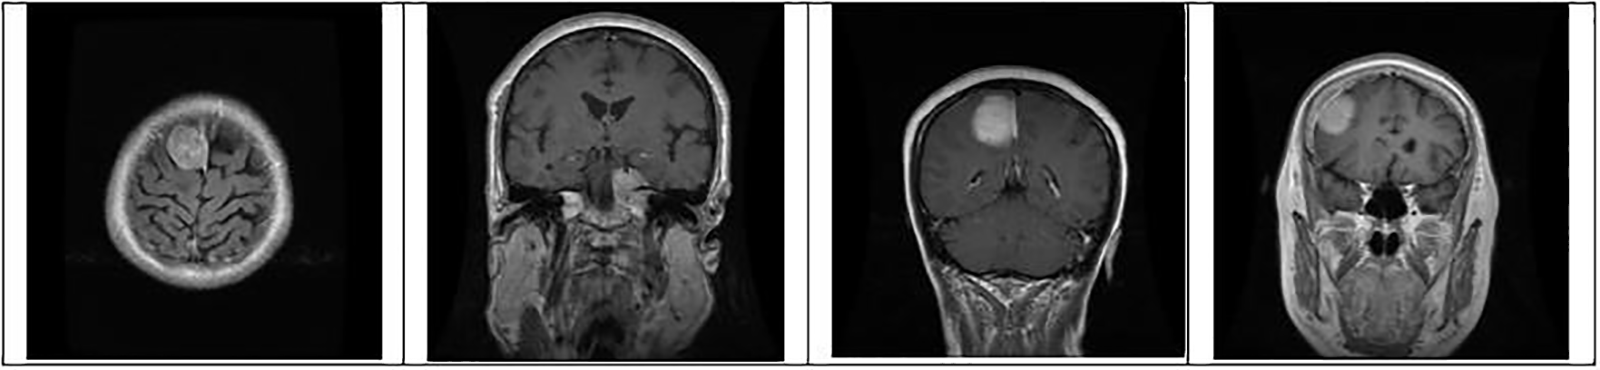

where pc is a package configuration of brain tumor algorithm, mf is making the file of brain tumor, and m is brain tumor contour make. Figs. 4 to 6 represent three different types of brain tumors: glioma, meningioma, and pituitary. With algorithm 1, all said types were identified. The output of different kinds of brain tumor detection and its sample is represented in Figs. 4 to 6. Here glioma is a low-grade tumor, like a normal brain, with a similar texture and colour. Here intra-operative sampling and the enhanced visual tumor have been applied as glioma detection steps, as shown in Fig. 4. For meningioma detection, vision change, seizures, and confusion were checked with dura mater and pia mater, as shown in Fig. 5. Here DeepMedic architecture with t1 method for MRI image. The same further process is applied to pituitary tumors. The EDLA architecture process was applied, and results were generated.

Figure 5: Identification of brain tumor-type meningioma samples from the dataset for training and testing